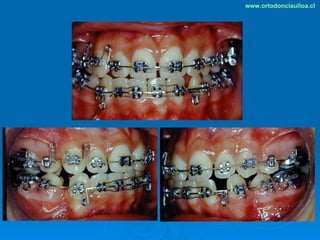

Este documento presenta dos casos clínicos de pacientes que recibieron tratamiento de ortodoncia. El primer caso fue de una paciente femenina de 14 años con apiñamiento dental y mordida cruzada que fue tratada mediante extracción de premolares y alineamiento dental. El segundo caso fue de un paciente masculino de 14 años con clase II esqueletal y desarmonía dentomaxilar que fue tratado con extracción de premolares y corrección de mordida. Ambos casos mostraron mejoría después de 3 años de tratamiento.